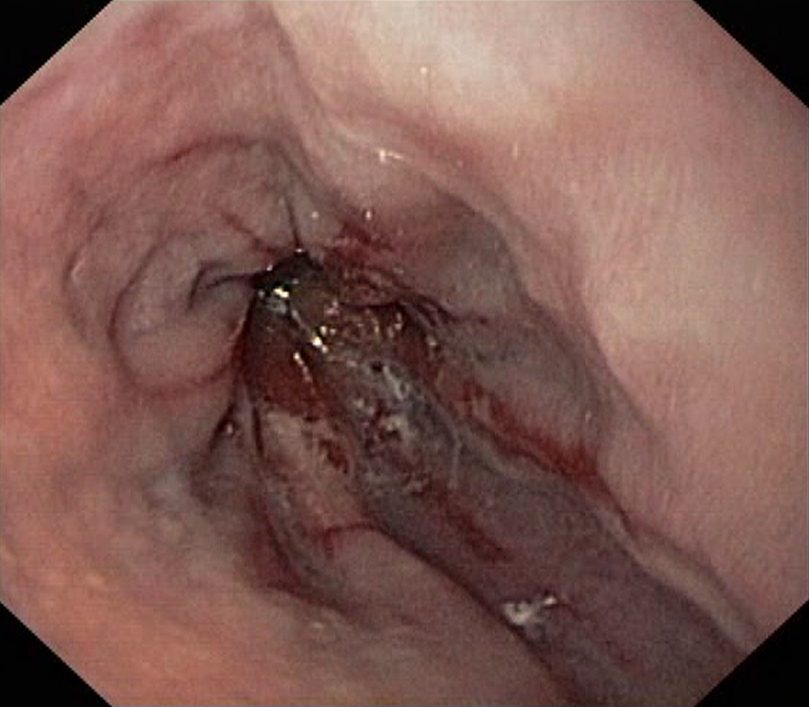

Reflux Oesophagitis Grade D (LA Classification). Just click on a picture!

Reflux Oesophagitis Grade D (LA Classification)